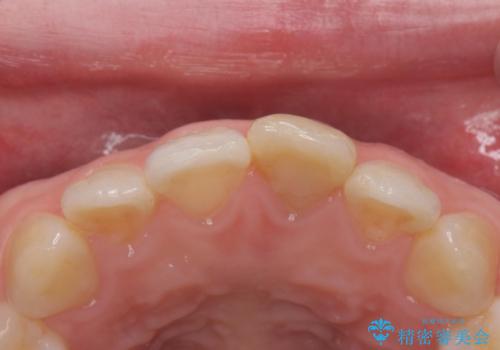

前歯の変色とガタつき ジルコニアクラウンでの修復

- 前歯の変色とガタつきが気になるとのことで来院された患者様です。

根管治療からやり直しを行った後、ジルコニアクラウンで修復することで、ガタつきと変色の両方を改善していきます。

ガタつきと変色の両方を改善することができ、大変喜んでいただけました。

少しのガタつきであれば、矯正治療を行わなくても改善できる場合があります。